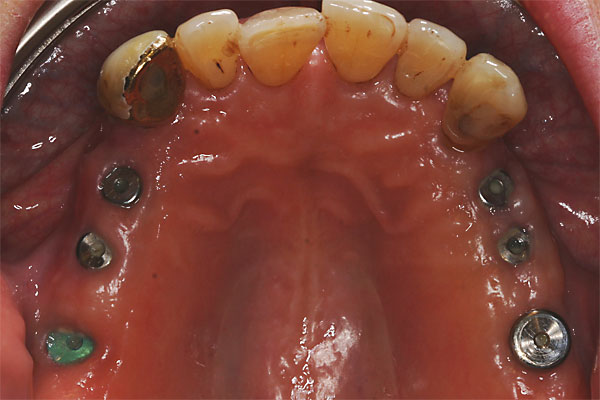

Fall: festsitzender Zahnersatz im Oberkiefer auf 8 Implantaten

FOTO Abdruckpfosten im Mund zur Übertragung auf das Meistermodell |